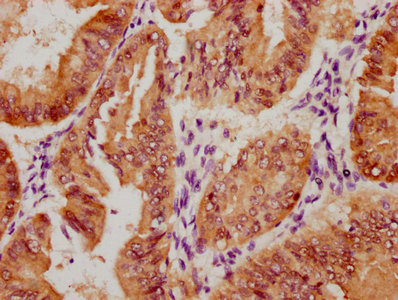

Western Blot

Positive WB detected in: Mouse liver tissue

All lanes: MAB21L2 antibody at 3μg/ml

Secondary

Goat polyclonal to rabbit IgG at 1/50000 dilution

Predicted band size: 41 kDa

Observed band size: 41 kDa -